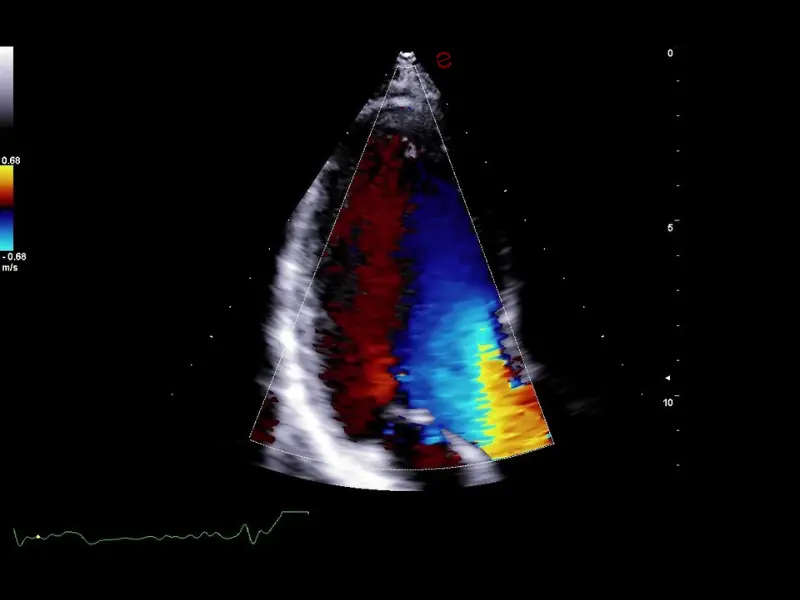

Q7 - Cardio CFM

Q7 - Cardio CFM